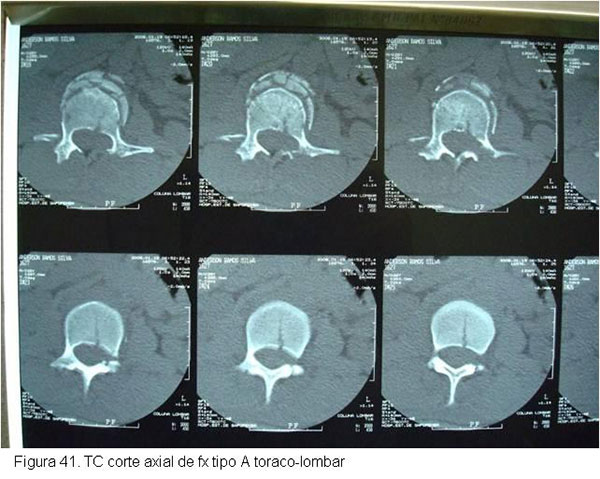

O tratamento seguirá o mesmo raciocínio discutido anteriormente, dependendo de quais estruturas estiverem lesadas. Particularidades da região toraco-lombar e lombar determinarão abordagens especificas caso a caso.(figuras 40, 41, 42 3, 44, 45)